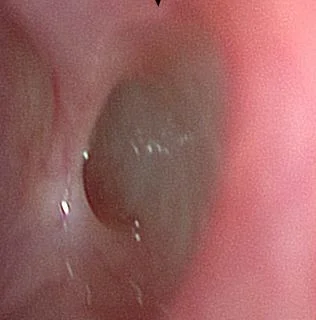

A 55 y.o. woman who has had sinus surgery comes in for epistaxis. When you scope her you see what is pictured below.

This is a remnant of our reptilian  ancestry called the vomeronasal organ(VNO)  or Jacobson’s organ. It is auxillary olfactory sense organ useful for detecting pheromones.  It was discovered in 1732 by Frederick Ruysch and later rediscovered by Ludwig Jacobson in 1813. In humans the organ, which is found along the nasal septum,  regresses during fetal development but can be seen in about 25% of adults.  Image below is from Chapter 41. Physiology of olfaction. DA Leopold and EH Holbrook. Cummings Otolaryngology. 5th edition.

close up of the Vomeronasal organ on the septum

Our patient was being scoped  for possible bleeding after sinus surgery.  Her vomeronasal organ is just a vestigial remnant  of evolution. It does not function in humans.  Our patient had no nasal bleeding and was found to have an ulcer.